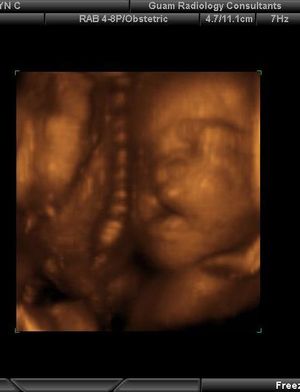

Cleft Lip and Palate Still 4D surface rendered imagePublished: June 17th 2011 | Updated: